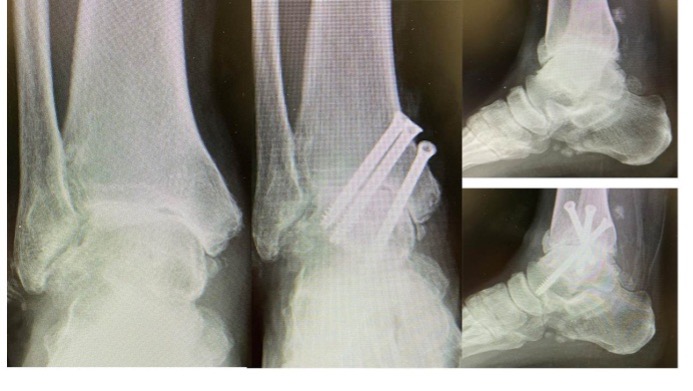

足関節障害に対する外科的治療

OA、RAの足関節障害には人工足関節置換術(total ankle arthroplasty: TAA)(図9)や関節固定術を行います。TAAは距踵病変がなく、比較的変形の少ない例に施行され、可動性を保つことができます。固定術は高度変形にも適応があり、関節の安定化が期待できます(図10)。RAは距踵関節にも破壊が生じやすいため、距腿関節と距踵関節(Tibio-talo-calcaneal: TTC)を同時に逆行性髄内釘で固定することもあります(図11)。

図9:人工足関節置換術

図10 足関節固定術

図11 RAの足関節障害に対するTTC固定術